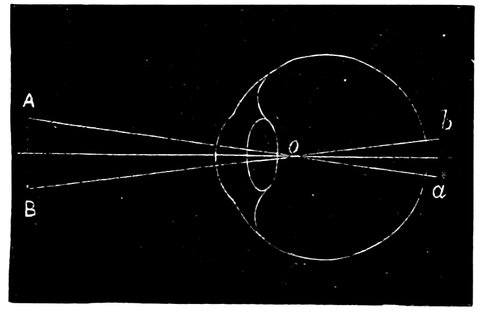

| 34. | Action of a long-sighted eye | 69 |

| 35. | Diagram showing path of rays when viewing an object at an easy distance | 70 |